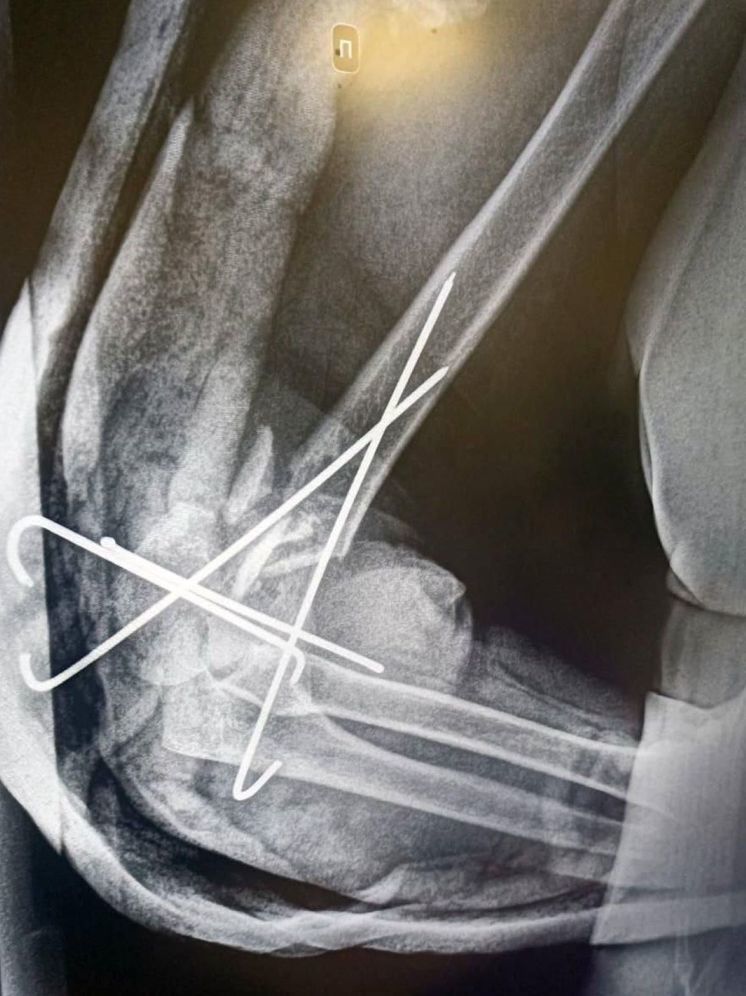

Фото: пресс-служба министерства здравоохранения Московской области

Врачи применили метод соединения обломков костей металлическими вставками, называемый остеосинтез. Таким образом, были прооперированы правое плечо, обе кости левого предплечья и большеберцовой кости. Хирургическое вмешательство длилось около 2-х часов, рассказал заведующий травмоцентра Долгопрудненской больницы Максим Цымбал. Послеопреационный этап у пациентки прошел успешно. В данный момент она выписана под амбулаторное наблюдение. Подвижность плеча у женщины восстановлена. На полную реабилитацию больной понадобится 2,5 месяца, уточнил источник.